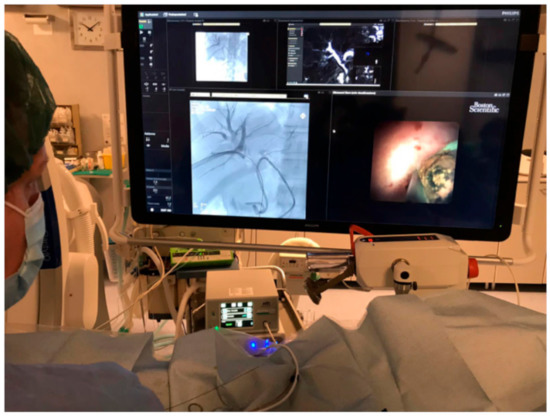

2.3. Technique and Procedure